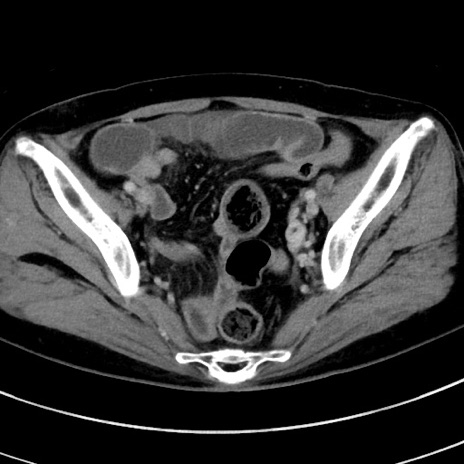

症例

冠状断像